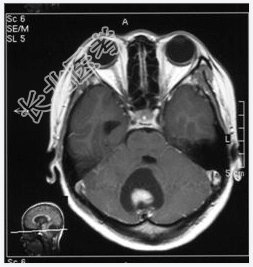

- [材料题] 患者,女性,19岁,因眩晕伴呕吐1周入院。体检:眼震,步态不稳,余未见异常。做头颅MRI检查。

- 简答题1、诊断及依据是什么?

- 简答题2、鉴别诊断有哪些?